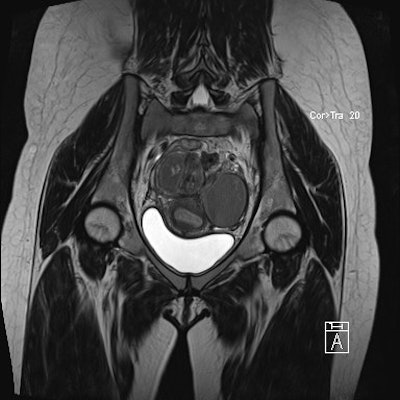

The study included 31 patients who were imaged using a 1.5-tesla MR system (Magnetom Avanto, Siemens Healthcare). They imaged in the supine position with a phased-array surface coil and received 20 mg of intravenous hyoscine butylbromide (Buscopan, Boehringer Ingelheim) just prior to imaging to minimize bowel peristalsis. High-resolution 3D T2-weighted images were obtained in the coronal plane.

Two experienced radiologists independently assessed image quality and disease extent in the 31 patients. Both were blinded to patient identity, previous imaging, and menstrual status. Interobserver agreement was assessed using the kappa (κ) test.